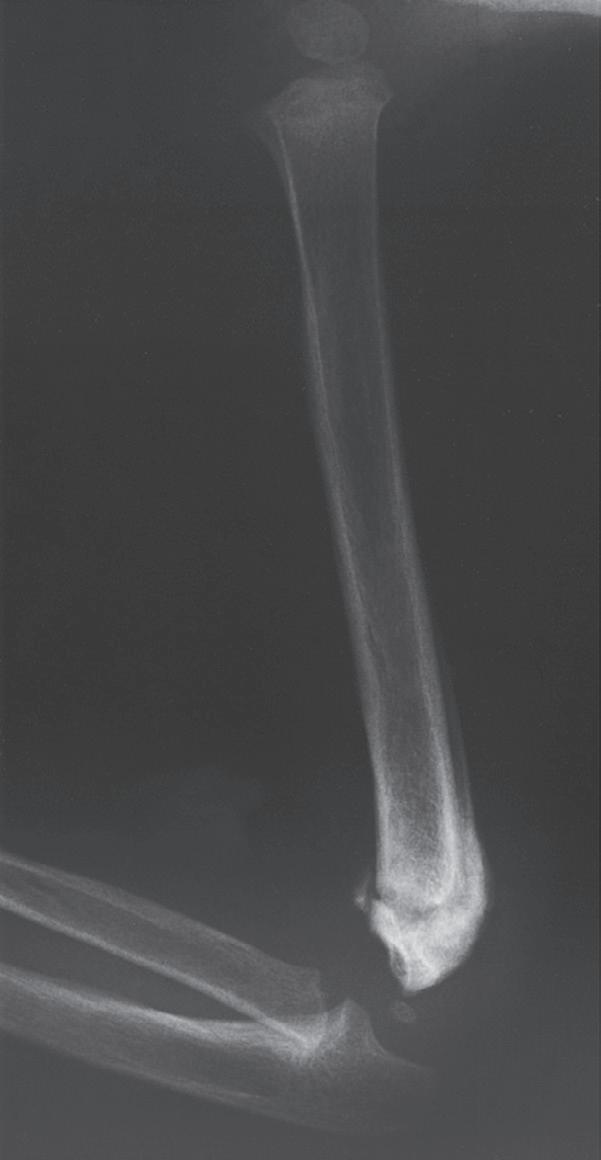

Tissue differentiation during the reparative phase is strongly influenced by local mechanical factors. Fracture stability has a critical effect on bone healing. Fracture healing is classically divided into primary and secondary healing. Primary healing results from rigid stabilization (i.e., plate immobilization) and involves a direct attempt by the cortex to bridge the fracture gap. Bridging occurs through direct haversian remodeling by intramembranous bone formation (Fig. 1.2A, B).

Secondary healing results from treatment of fractures with less rigid methods (i.e., fracture bracing, casts). In secondary healing, more motion at the fracture site leads to lower

Fig. 1.2 Anteroposterior (A) and lateral (B) radiographs of a forearm in a 15-year-old male who underwent open reduction and internal fixation with plates/screws. The fracture healing demonstrates primary bone healing with rigid fixation. An anteroposterior radiograph of a forearm in a 5-year-old at the time of original cast immobilization (C) and at 10 weeks (D) with complete fracture union demonstrates secondary bone healing. The motion that occurs with secondary bone healing results in abundant callus formation.

oxygen tension, and more cartilage is formed. Motion at the fracture site, the presence of a fracture gap, and an intact soft tissue envelope all encourage the formation of abundant callus (Fig. 1.2C, D). The increased diameter of the callus enhances biomechanical stability because the rigidity of the bone is proportional to its radius. The callus formed subsequently undergoes endochondral ossification. Ideal fracture treatment involves enough rigidity to ensure adequate vessel ingrowth, followed by progressive loading and motion to stimulate ample callus formation.36,40